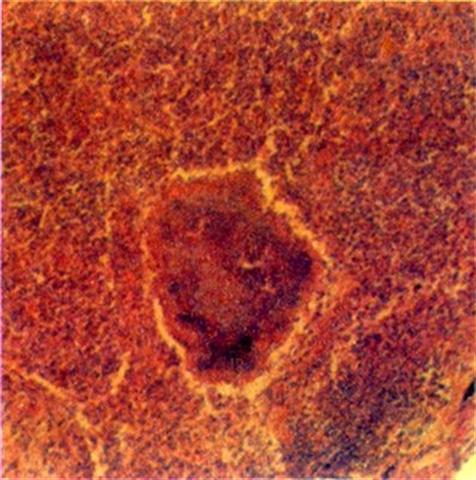

Рис. 2. Микропрепарат легкого при актиномикозе на фоне пневмонии: альвеолы заполнены организующимся экссудатом, в центре поля зрения — друзы актиномицет. Окраска гематоксилином и эозином; ´100.